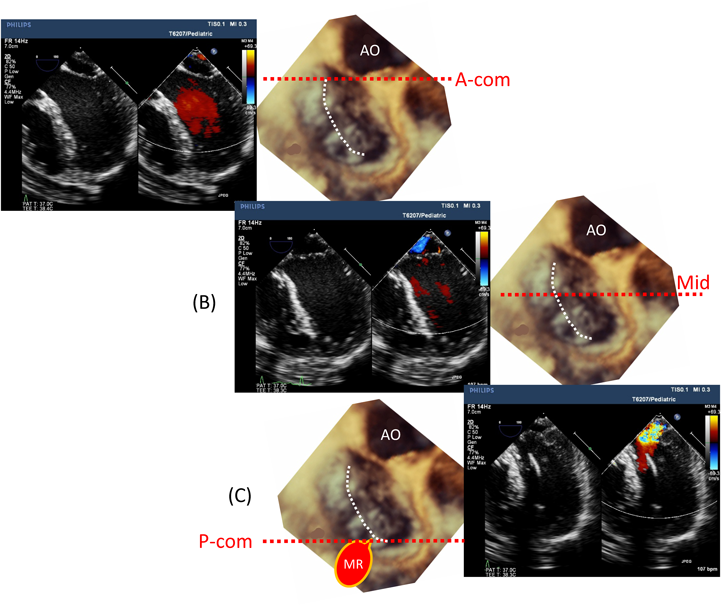

GEヘルスケア・ジャパン、新製品LOGIQ Totusを加えたLOGIQ, 房室弁の心エコーによる解剖学的評価「症例別 周術期3D経食道心エコーアトラス」Wei-Hsian Yin / Wei-Hsian Yin / Ming-Chon Hsiung / 春日武史定価: ¥ 10000#WeiHsianYin #Wei_Hsian_Yin #WeiHsianYin #Wei_Hsian_Yin #MingChonHsiung #Ming_Chon_Hsiung #春日武史 #本 #自然/医療・薬学・健康--新品を裁断済みです。【koro】イラスト解剖学 改訂10版 最新版。書き込みありません。食品添加物インデックスPLUS : 和名・英名・E No.検索便覧。

房室弁の心エコーによる解剖学的評価「症例別 周術期3D経食道心エコーアトラス」Wei-Hsian Yin / Wei-Hsian Yin / Ming-Chon Hsiung / 春日武史定価: ¥ 10000#WeiHsianYin #Wei_Hsian_Yin #WeiHsianYin #Wei_Hsian_Yin #MingChonHsiung #Ming_Chon_Hsiung #春日武史 #本 #自然/医療・薬学・健康--新品を裁断済みです。【koro】イラスト解剖学 改訂10版 最新版。書き込みありません。食品添加物インデックスPLUS : 和名・英名・E No.検索便覧。